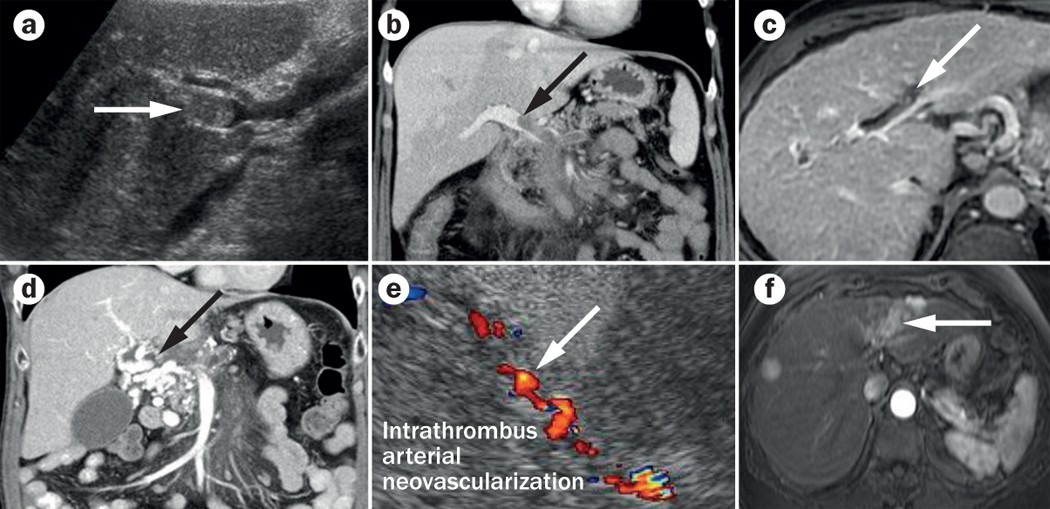

Imaging In Clinical Decision Making For Portal Vein Thrombosis Nature Reviews Gastroenterology Hepatology